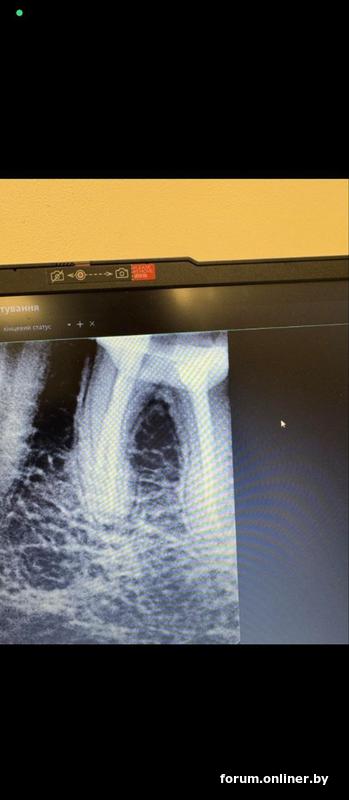

Вот это фото из клиники, которое прислали по запросу, не ясно какое до перепломбировки, какое после. Вот так и выслали, как фото с компьютера. Может будет полезно. Но первое с потемнением более свежее, а это старше где то сразу после лечения или в процессе или до, врач не уточнил и дат на фото нет.

Вот места на актуальном фото которые особенно интересуют человека.